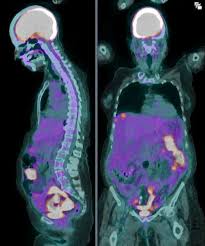

A DOTA PET scan and an FDG PET scan are used for different clinical purposes. DOTA PET scans are designed to detect tumors that express somatostatin receptors, most commonly neuroendocrine tumors, and are performed only when specifically recommended by a doctor.

In contrast, an FDG PET scan measures glucose metabolism and is widely used for evaluating many types of cancers and inflammatory conditions. While FDG PET is suitable for general oncologic assessment, DOTA PET imaging provides more targeted and precise information for receptor-specific diseases.

A DOTA PET scan is primarily used to evaluate neuroendocrine tumors and related conditions that express somatostatin receptors. It helps in identifying the primary tumor site, detecting metastasis, and assessing disease extent with high accuracy.

This scan is commonly recommended for conditions such as gastroenteropancreatic neuroendocrine tumors, bronchial carcinoids, and other receptor-positive neuroendocrine malignancies, where targeted imaging is essential for clinical decision-making.